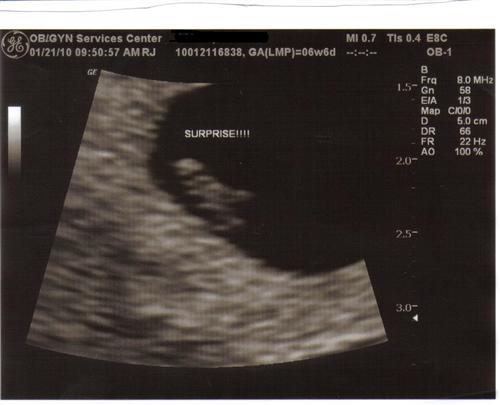

It's confirmed....

I am definately joining the 2 under 13 months group! I went for my first sono on Thursday & we have a heartbeat!!!! Right now i am measuing 6w6d with a due date of 9/12. DH & I are still in shock but so happy! We go back 2/26 for our ultrascreen!!! Here is our little bean